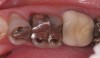

(7.) “Ditching” from GERD around existing restorations may be noted upon examination.

Figure 7